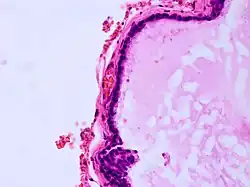

Histopathology of colloid cyst